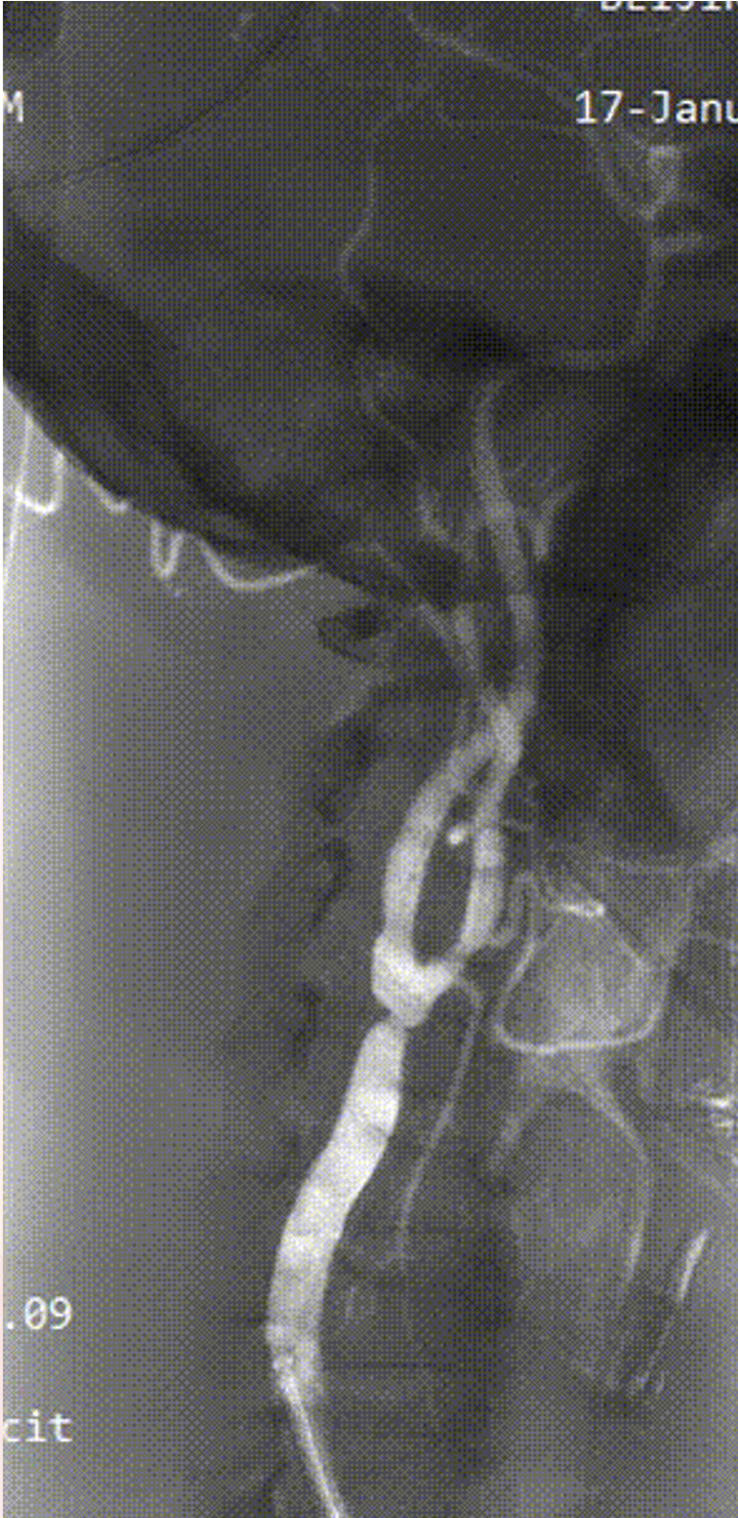

病例3:62岁男性,发作性胸痛9个月,外院行PCI后仍有症状,拟冠脉搭桥前发现双侧颈动脉狭窄,行双侧CAS,先右后左,3个月后行左侧CAS,术后复查彩超显示支架通畅,1个月后行冠脉搭桥手术。

右侧术前

右侧术后

左侧术前

左侧术后